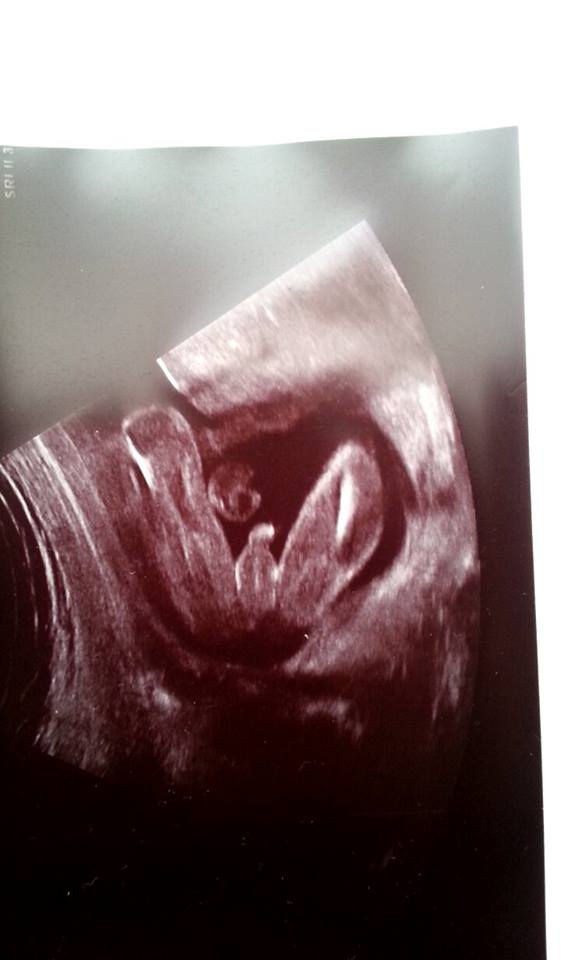

Je to holčička nebo chlapeček? Foto ultrazvuku

@zuziry : na tohle ti rekla holcicku ?? 🙊tak uvidíš třeba ji met budeš. ... já tam vidím výstavního pindika...i s kuličkami,ale jestli ti to řekla tak třeba holčičku mít budeš 😉ten 20 týden je docela přesný pokud jsou nožičky takhle zepředu. A kdyby to byl kluk,tak nevěš hlavu,ja tenkrát i plakala a dnes bych ho nevymenila za nic na světě, mám totiž také 3kluky...😉

@satynka Mně je pohlaví jedno 🙂. No ale jak jsem doma koukala na tu fotku, tak se mi taky zdá že to je kluk. Leda že by to byl kousek bříška, ale to se mi nezdá tak symetrické ( vyznačím to )...

Tak ještě jak to vidím já 🙂, třeba to i pomůže někomu se lépe orientovat ve vlastních fotkách 😉

tady je hezky znázornění,ze může byt pindik i kavove zrno,😃myslím tím ty kuličky. ..ale říkáte ze je to kluk,tak to kluk je,myslím ze je to moc hezká fotecka 👍😉

@jadupka ty jo to je blba fotka.. Takhle to je kluk, prostě tam něco visí,ale stejně nevim z jakého úhlu na to kouknout..